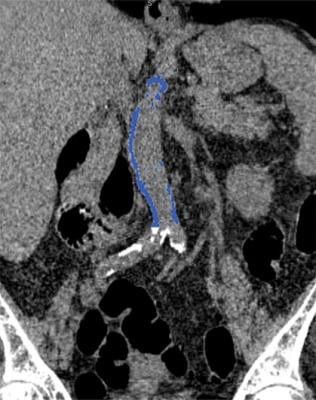

Images from computed tomography (CT) colonography show segmented abdominal aortic calcification measured with semiautomated CT tool on coronal image. Within region of interest over aorta selected by user, tool automatically segments and quantifies aortic calcification (shown in blue).

Image Credit: O’Connor S D, Graffy P M, Zea R, et al. Does nonenhanced CT-based quantification of abdominal aortic calcification outperform the Framingham Risk Score in predicting cardiovascular event sin asymptomatic adults? Radiology doi: 10.1148/radiol.2018180562. Published online Oct. 2, 2018. © RSNA.

CT can also measure calcium in the abdominal aorta, the large vessel that carries oxygenated blood to the lower extremities. The abdominal aorta can be seen on abdominal imaging exams like CT colonography, also known as virtual colonoscopy, and in the diagnostic workup for acute cholecystitis, an inflammation of the gallbladder often caused by gallstones.